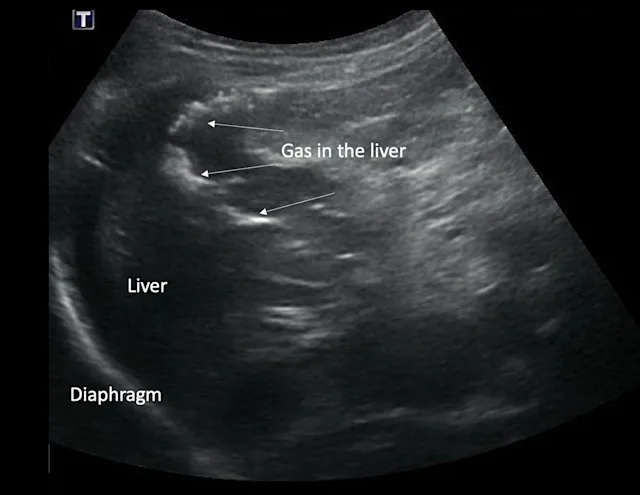

Abdominal radiography is important in the diagnosis of hepatobiliary disease, as it can help detect abnormal liver size and shape and identify mineralization or gas in the liver or intra- and extrahepatic biliary tract. Abdominal ultrasonography is the most useful noninvasive diagnostic tool for differentiating hepatic from posthepatic causes of icterus, obstructive from nonobstructive biliary disease, and diffuse from focal hepatic parenchymal disease.1

Ultrasonography is useful for estimating hepatic size and evaluating internal architecture (including portal, venous, arterial, and biliary vasculature; echogenicity; and echotexture). Size, wall thickness, and contents of the gallbladder, as well as size of the bile ducts, can also be assessed. Ultrasonography is also helpful for differentiating chronic injury (eg, cirrhosis, end-stage chronic inflammatory disease) from acute liver injury based on the size, shape, and internal architecture of the liver parenchyma.2